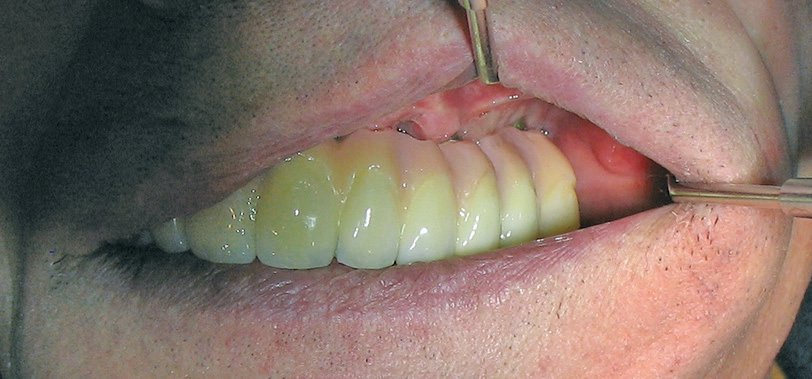

Für die Suprakonstruktionen wurde das Sekundärgerüst auf Abutment-Niveau gefräst. Der Patient bekam im Oberkiefer ein System mit interner Sechskantverbindung (Abb. 9-16). Die Patientin im Unterkiefer bekam ein System desselben Herstellers mit konischer Abutmentverbindung (Abb. 1-8). Davon ist ein Implantat noch in der Einheilphase verloren gegangen. Der betroffene Kiefer konnte trotzdem mit fünf Implantaten versorgt werden. Vom Prinzip „all-on-4“ wurde bewusst Abstand genommen. Ebenso wurde auch auf geneigt gesetzte Implantate verzichtet. Die Implantate, die abgewinkelte Abutments bekamen, wurden nach den prothetisch und anatomisch günstigsten Knochenverhältnissen gesetzt.